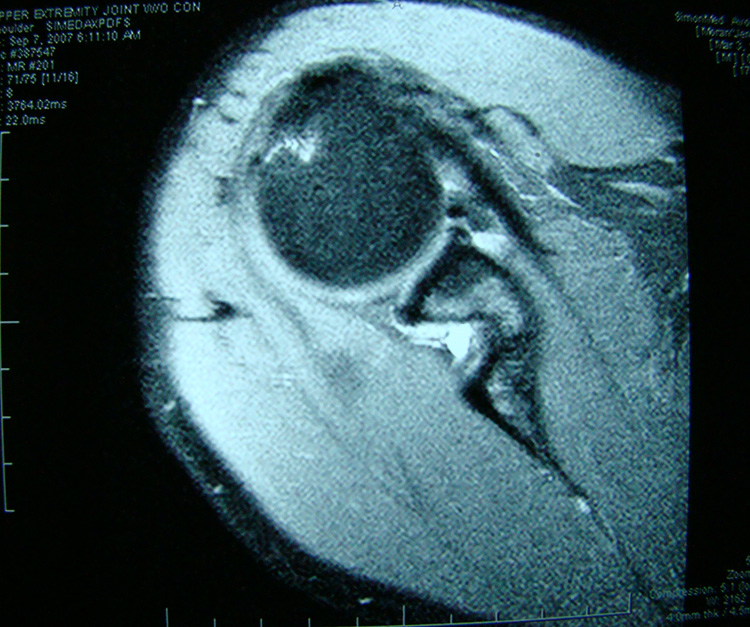

This patient presented with shoulder pain that interfered with work and exercise. The visible fluid-filled cysts on the “Before" MRIs are from chronically injured rotator cuff tendon roots.

The patient underwent treatments of a highly specialized fine-needling technique pioneered by Dr. Tallman.The follow-up MRI was done 2 months after his 6th treatment. He was released with a pain-free, full range of motion with unrestricted activities.